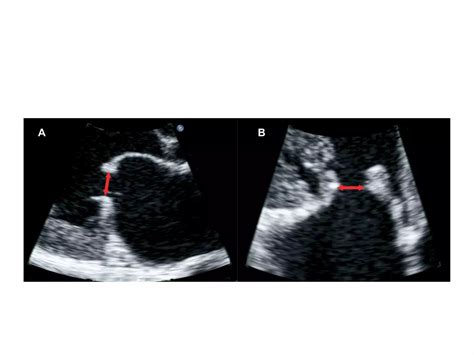

Valve Morphology: The shape and structure of the mitral valve are examined to determine the extent of narrowing and any signs of calcification or thickening.

Valve Area: The area of the mitral valve opening is measured. A normal valve area is typically around 4-6 cm². In mitral stenosis, this area is significantly reduced, often to less than 2 cm².

Left Atrial Size: The size of the left atrium is evaluated. In mitral stenosis, the left atrium often enlarges due to the increased pressure.